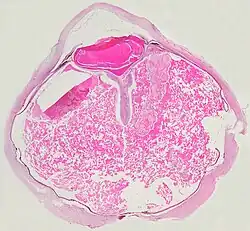

Как правило, макроскопически видны отслоение сетчатки и желтоватый субретинальный экссудат, содержащий кристаллы холестерина.

Микроскопически, стенки сосудов сетчатки могут утолщаться в некоторых случаях, в то время как в других случаях стенки может быть истончены с нерегулярным расширением просветов[11]. Субретинальный экссудат состоит из кристаллов холестерина, макрофагов, нагруженных холестерином и пигментом, эритроцитов, и гемосидерина[12]. Гранулёматозную реакцию, индуцированную экссудатом, может быть видно в сетчатке[13]. Фрагменты сетчатки могут развивать глиоз в ответ на повреждение.